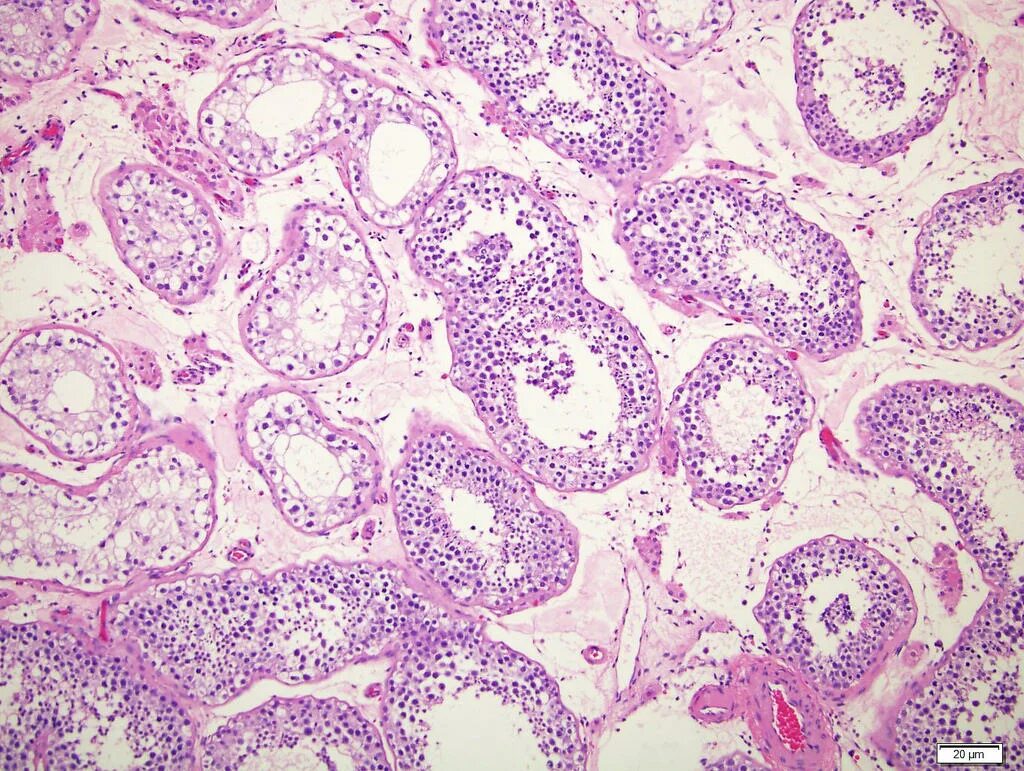

Гистологическая картина